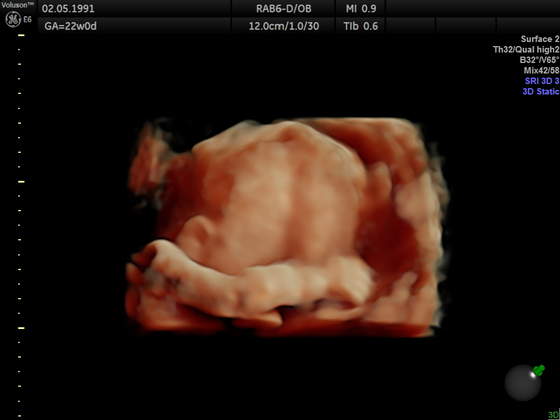

Wciąż mam tylko więcej leżeć niż chodzić i ograniczać jakieś gwałtowniejsze ruchy . Potwierdziła nam się CÓRCIA, już na 100%, byliśmy na usg 4d jestem mega zadowolona same badanie trwało ok. godziny wszyściutko pomierzone, posprawdzane, przepływy, serduszko, kości - wszystko prawidłowe, mega miły lekarz. Malutka waży 375 gram i tak się wierciła przez całe badanie że nie dawała sobie zdjeć cykać i zasłaniała sie rączkami, zresztą ostatnio jakas w ogole nadaktywna bo co chwile mnie puka w brzuszek